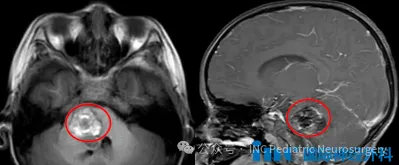

每个家长最担忧的,莫过于孩子突发疾病,尤其是毫无预警的严重病症。三岁的小女孩艾米娜(化名)原本活泼好动,却突然变得嗜睡、哭闹并诉说头痛,随后还出现右侧面部歪斜、肢体无力,甚...

经检查确诊男孩患有海绵状血管瘤。虽然该病变属良性性质,但可能引发脑干出血,导致瘫痪、功能永久性损伤甚至死亡等严重并发症。然而病情恶化速度超出预期。...

更新时间:2025-12-02 09:11:36